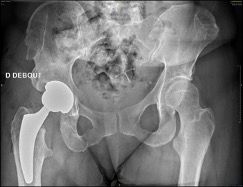

4. Value of a short stem in cases of sequelae of osteotomy, femoral curvature or narrow femur

While the initial goal is to restore the preoperative anatomy as closely as possible, it may have undergone changes due to fracture malunions, pathologies or surgical interventions, especially osteotomy, making it complex to open the femoral shaft. Sometimes, it is simply the native morphology of the femur that is unusual and requires technical consideration from the surgeon. It may in these cases prove very useful to choose a short stem (Figs 7 and 8). These are less common indications but they are worth mentioning.